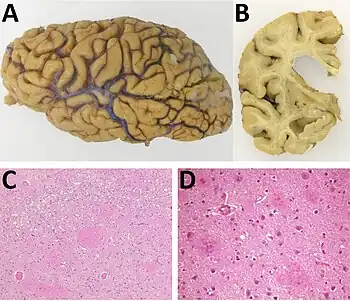

| a) Examination of the brain showing cortical brain atrophy b) coronal slide demonstrating severe cortical and subcortical atrophy c,d) microscopic anatomopathological analysis of the brain | |